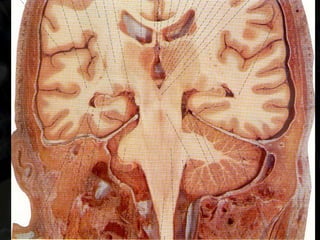

2. Cápsula Interna (AVC)

-Fraqueza completa, proporcional e contralateral. Alteração da sensibilidade